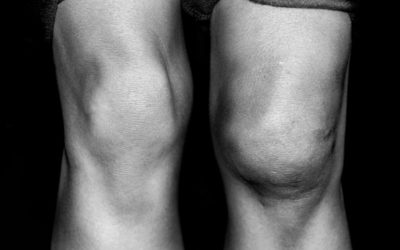

read moreRepairing Damaged Articular Cartilage

During the course of a lifetime, the human knee joint handles tremendous stress. From daily activities to intense sports, the knee joint effectively withstands compressive and sheer forces, but injuries can occur.